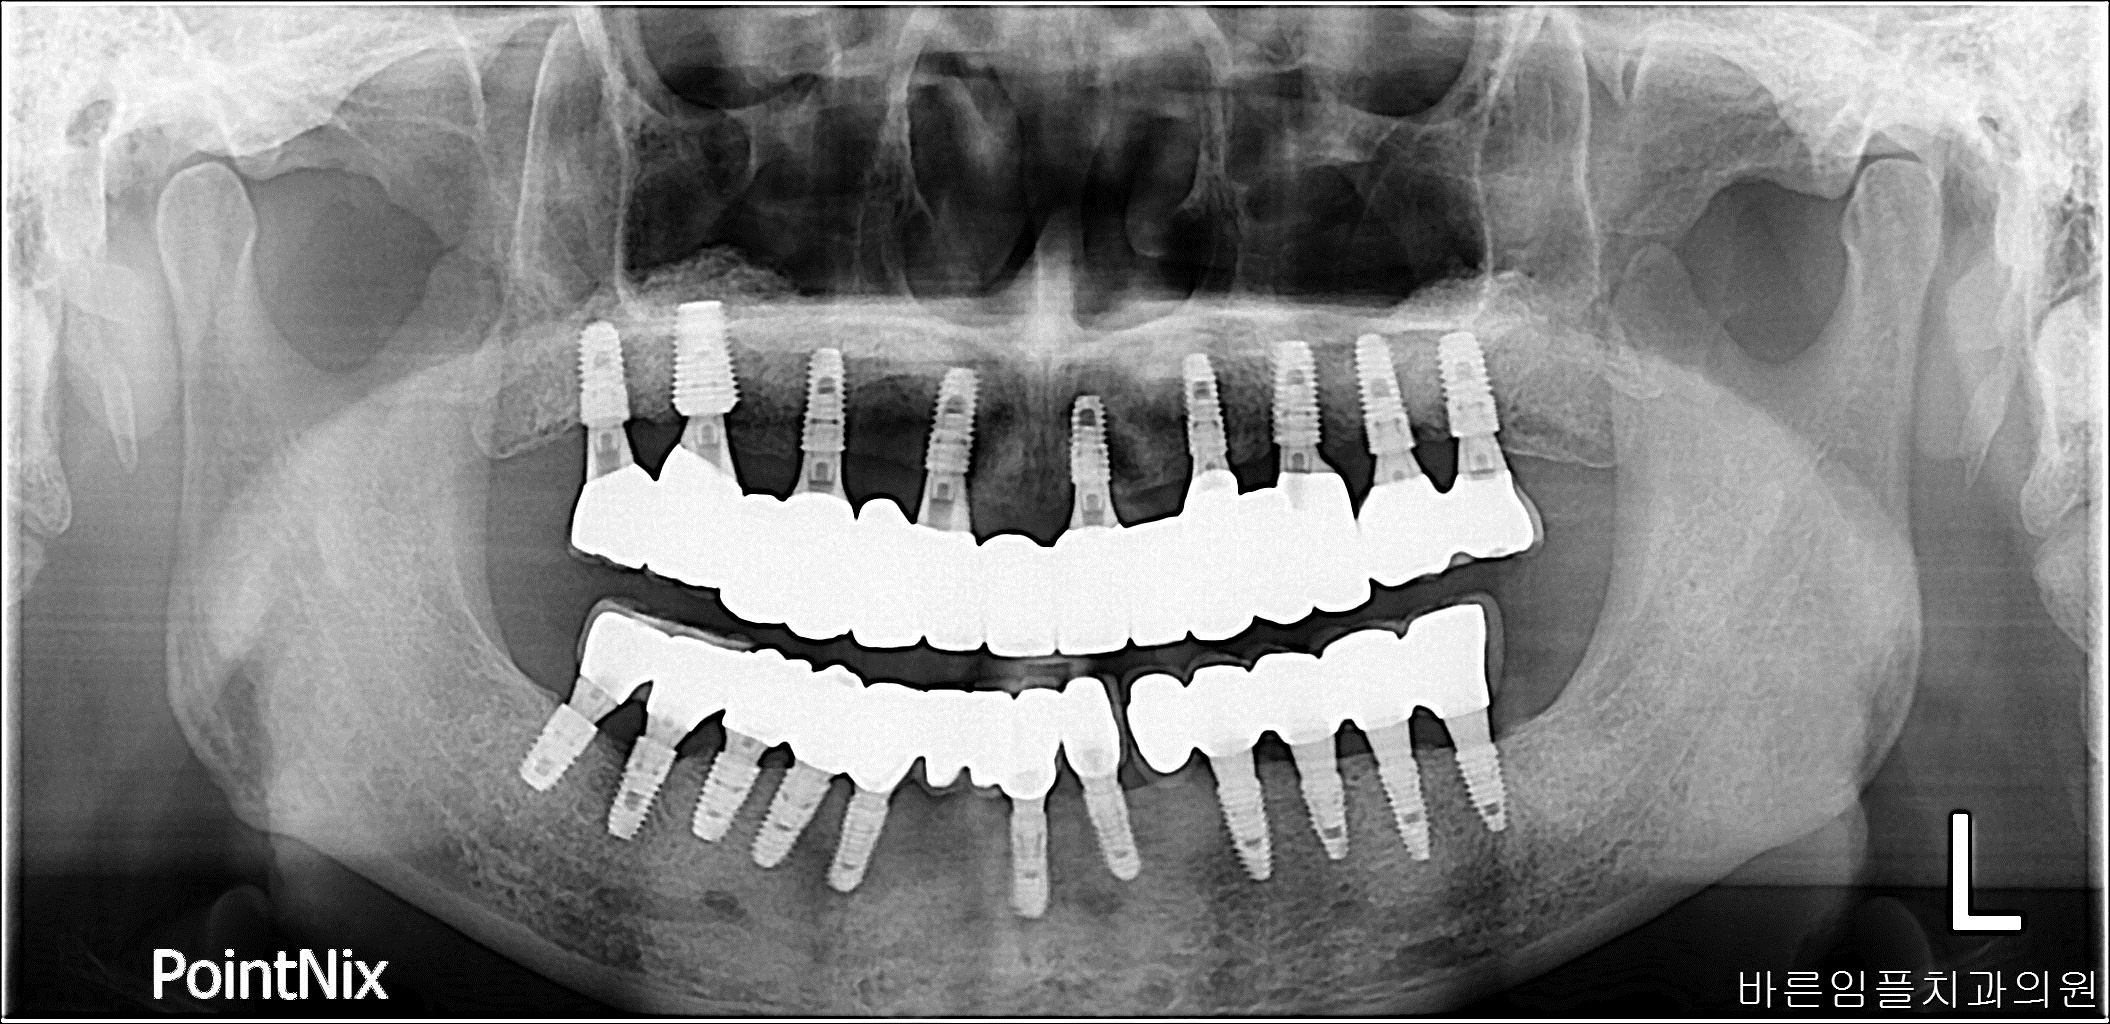

김ㅇㅇ / 수면임플란트 페이지 정보 작성일 23-10-27 17:01 2022-10-26 김ㅇㅇ Before 2023-09-02 김ㅇㅇ After 김ㅇㅇ / 수면임플란트 목록 이전글남ㅇㅇ / 임플란트 다음글 김ㅇㅇ / 임플란트